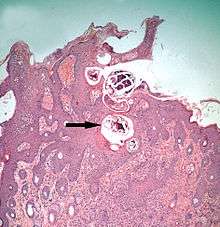

- Demodectic mites feed in a position technically external to the skin, between the epidermis and the hair shaft in hair follicles.

Demodicidae

One genus of mites, Demodex, has adapted to infesting the hair follicles of its hosts.[22] These mites remain external to the true outer layer of the skin (the epidermis) which also lines the tube of the hair follicle. However, the mites appear to be deep within the skin in the sense of being below the general outer surface of the host. The mites fit in the narrow space between the hair and the tube of the follicle. They may also crawl out onto the general epidermal surface of their host. Transmission of these mites from host to host occurs during close contact when young animals are suckled. Demodex mites are morphologically adapted to this constricted habitat: microscopic, worm shaped, and with very short legs. The mites feed on cells of the epidermal lining of the hair follicle. Many species of mammals, including humans, are readily infested with these mites, but typically the density of infestation is very low, and the mites can be more commensal than parasitic.[23]

Demodecosis

Demodecosis in cattle caused by Demodex bovis can occur as dense, localized infestations with inflammation of the epidermis in hair follicles.[36] This leads to pustular folliculitis and indurated (thickened) plaques within the skin. On cattle, these localized foci of infestation can become so large as to be clearly visible externally. The value of the hides from cattle infested this way is reduced.[37] Pigs may be similarly affected by infestations with Demodex.[38]